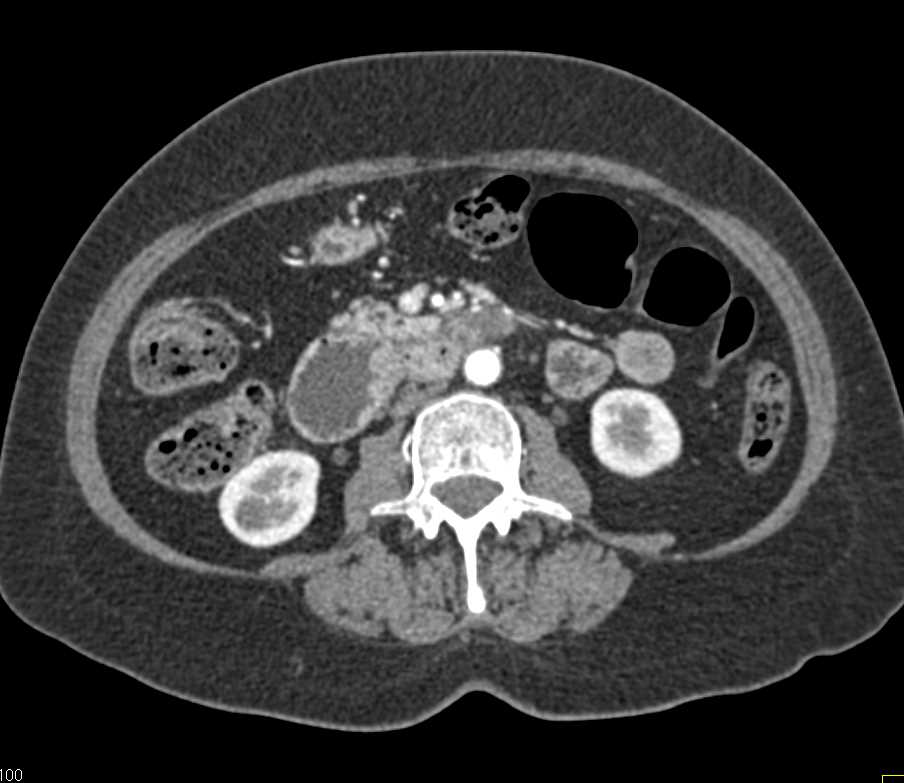

Small Bowel Carcinoma with Carcinomatosis